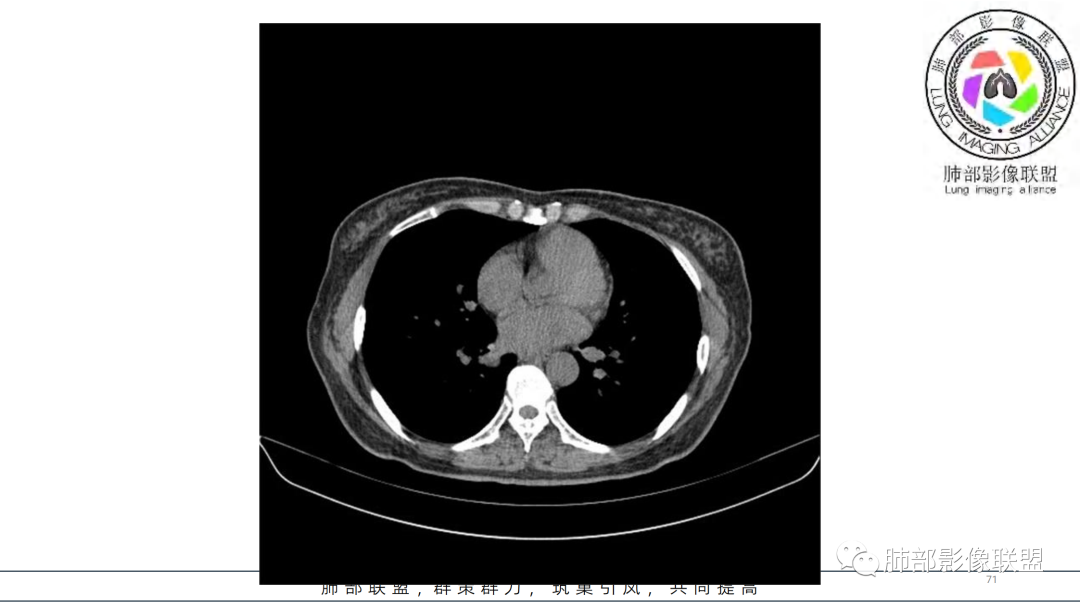

2.右肺下叶及中间段支气管后方类圆形块影,边界较清楚,未见分叶及毛刺,病灶部分突入支气管腔内(冰山一角),局部管腔狭窄,相应肺叶未见片影或体积变化。

3.块影密度均匀,未见液化坏死及钙化,渐进性强化,强化显著。

4.双肺门及纵隔未见增大淋巴结。未见胸腔积液。

综合分析:

中青年女性,支气管管腔内外肿块(“冰山征”),边界较清楚,强化显著,未见阻塞性肺不张,尽管未出现“类癌综合征”临床表现,仍然符合典型类癌影像学表现。